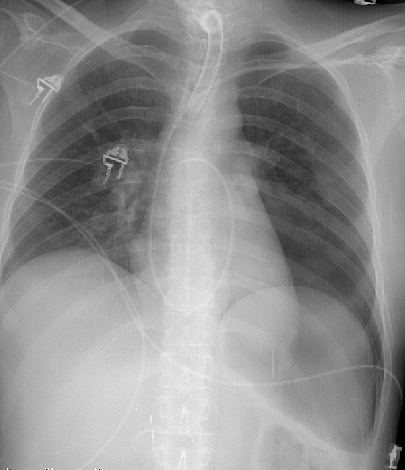

Gallery Blunt Chest Trauma Pneumothorax 2 deep sulcus

2 deep sulcus